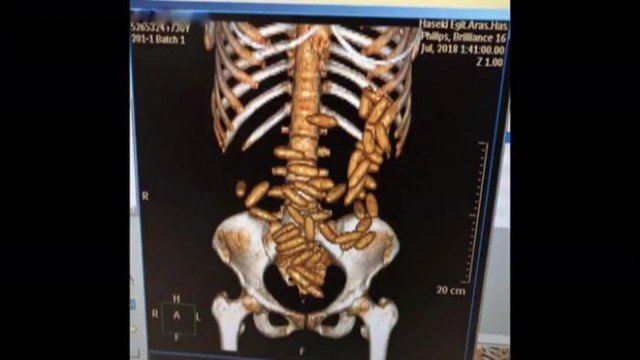

Uma brasileira foi presa no aeroporto de Istambul, na Turquia, ao ser flagrada com mais de 50 cápsulas de drogas escondidas no estômago.

O caso aconteceu no dia 27 de julho, mas só foi divulgado nessa quinta-feira (1), pelas autoridades do país. De acordo com a polícia local, a mulher carregava no total, mais de meio quilo de cocaína no corpo.

Ela foi levada para um hospital, onde a substância foi removida, em seguida foi encaminhada para a prisão. Conforme informações da Diretoria de Segurança da Divisão de Crimes de Narcóticos de Istambul, a brasileira teria partido de São Paulo. A embaixada brasileira na Turquia deve acompanhar o caso.